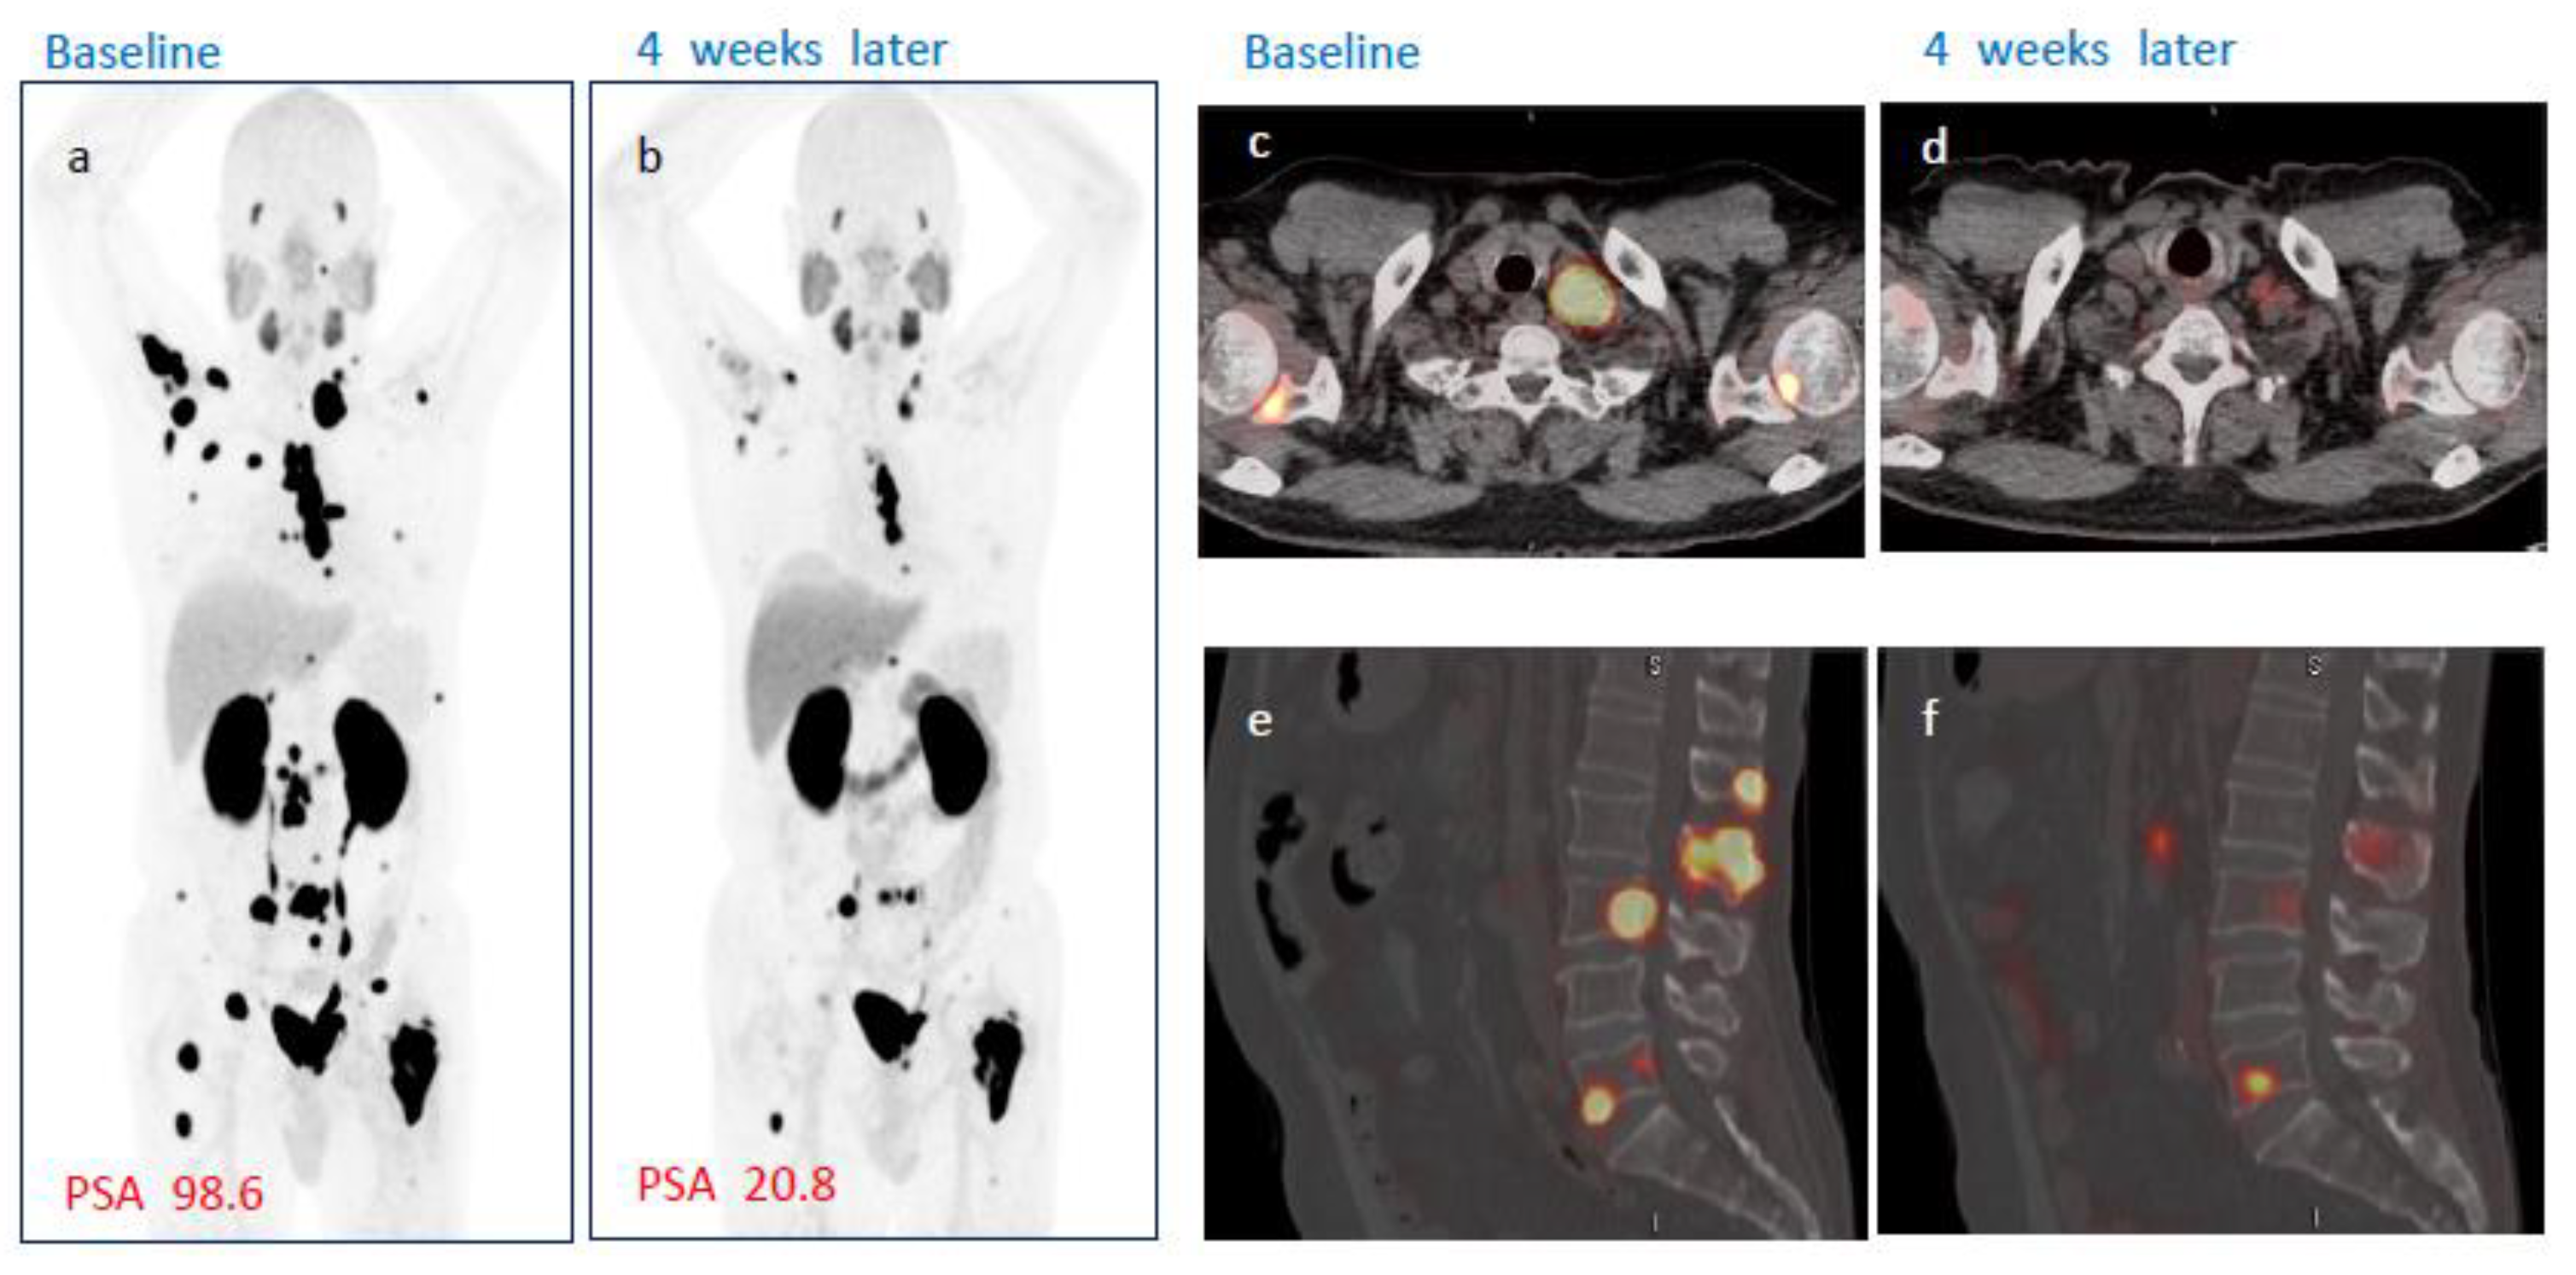

3.5. Radiological Assessment